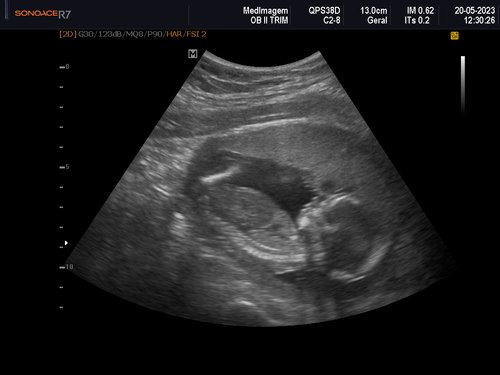

Eu tenho 27 anos estou grávida de 4 meses essa é a minha quarta gestação as minhas três últimas gestações eu perdi os bebês nunca consegui levar a gravidez adiante, eu quero muito conseguir levar essa, MINHA GRAVIDEZ É DE ALTO RISCO.

Uma amiga me deu a ideia de fazer uma vaquinha online, para conseguir fazer o tratamento no particular e o parto também, com ajuda de alguns amigos consegui arrecadar um valor e começar o tratamento no particular tive uma consulta com uma médica maravilhosa doutora Rochelle Hygino que na primeira consulta já me encaminhou para internação e para cirurgia, precisei fazer uma cerclagem no útero que é costurar o útero para segurar o bebê.